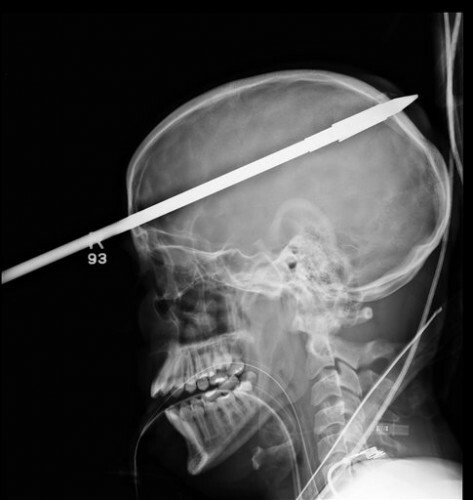

Florida teen recovering after being shot through head with spear

A FLORIDA TEENAGER is recovering in hospital after he was accidentally shot through the head with a spear by his friend during a fishing trip.

Doctors at the Jackson Memorial Hospital’s Ryder Trauma Center said yesterday that it took three hours to remove the spear from the 16-year-old’s brain.was rushed to hospital earlier this month with about 36 inches (3 feet) of spear protruding from his head. The projectile was accidentally fired by his friend as he was loading a spear gun.

The spear entered his forehead about two inches above his right eye and went through the back of his skull. Part of the visible section of spear was cut off to allow the teen to undergo cranial scans.

Doctors at the Jackson Memorial Hospital’s Ryder Trauma Center said yesterday that it took three hours to remove the spear from the 16-year-old’s brain.

The spear passed through the right hemisphere of his brain, missing major blood vessels, and doctors believe he could make a close to full recovery, ABC News reports. Although he does not remember the incident, the teenager has woken from his surgery and has spoken a few words.